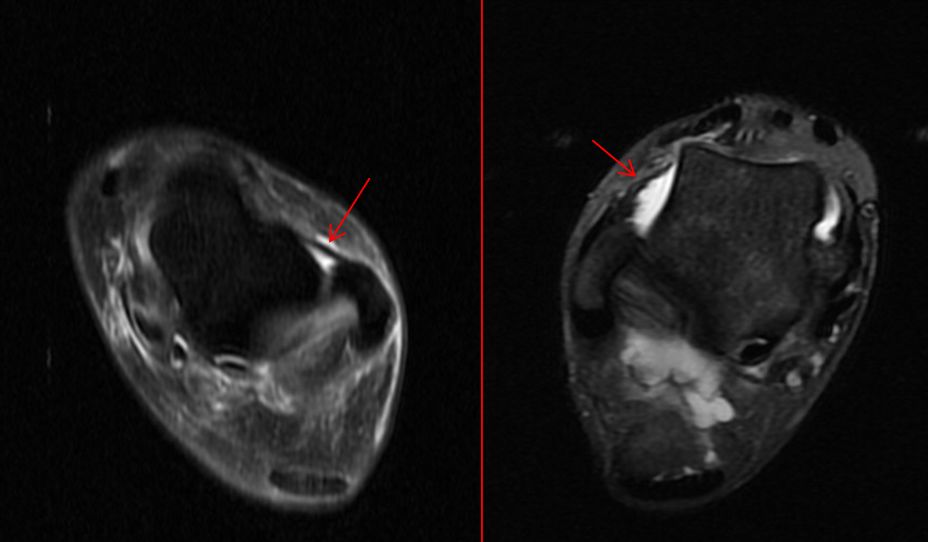

上图为距腓前韧带I度及II损伤